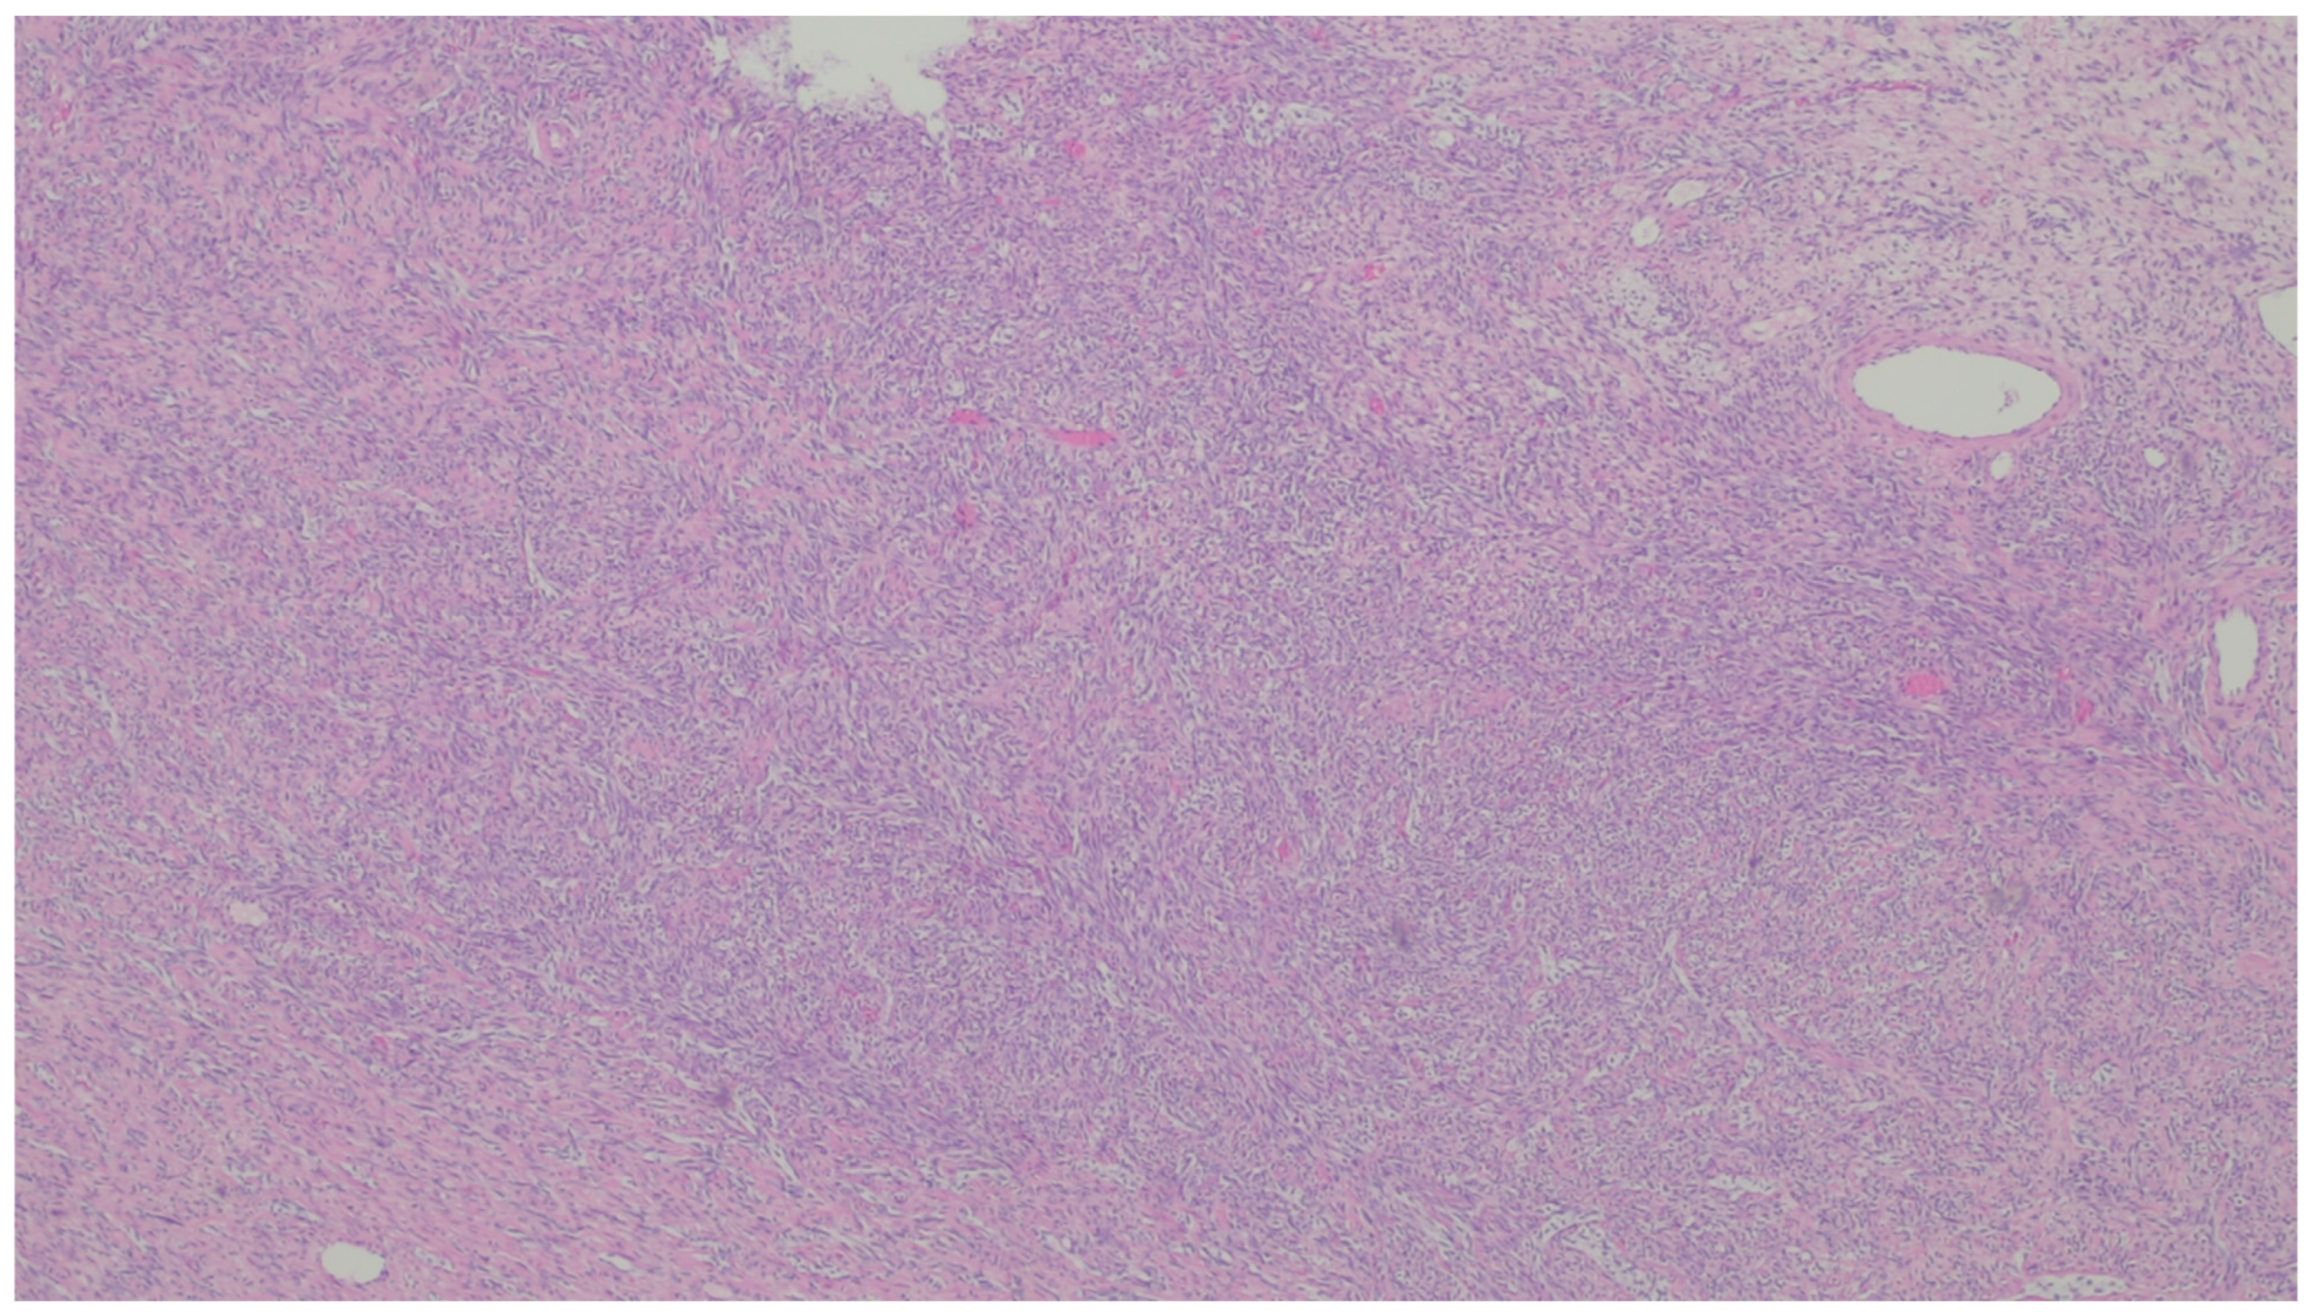

| Fibromatosis | 30 and 40 years | Mesentery of the small bowel | Abdominal pain | Long fascicles of spindle cells with ovoid nuclei without atypia or necrosis | Β-catenin |